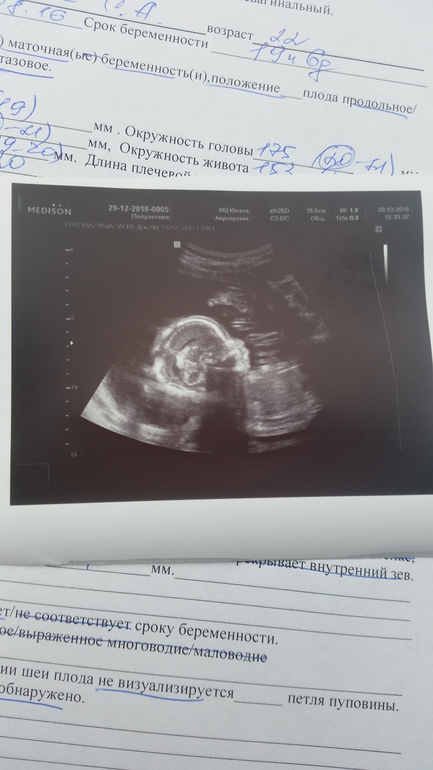

шейка 4.5 см, внутренний зев закрыт, плацента в норме. весит наш король 330 гр) ну и фото, вот не думала что уже в 20 недель можно быть копией папы

забавно. Родится посмотрим)